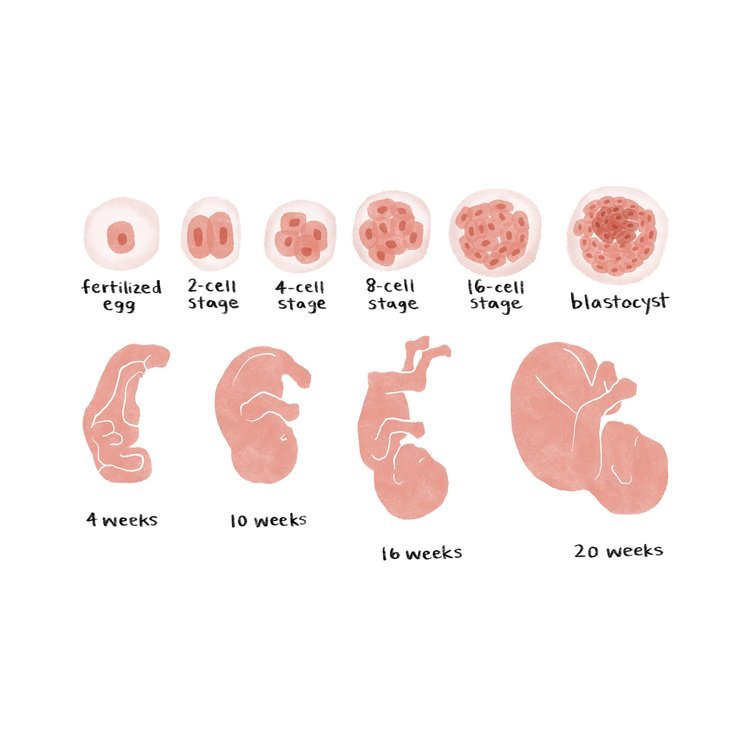

I created watercolor-style digital illustrations for an educational series on reproductive health called “How to Start a Family” for parents.com.

Digital watercolor artwork, 2022.

Embryo development

Fetal development